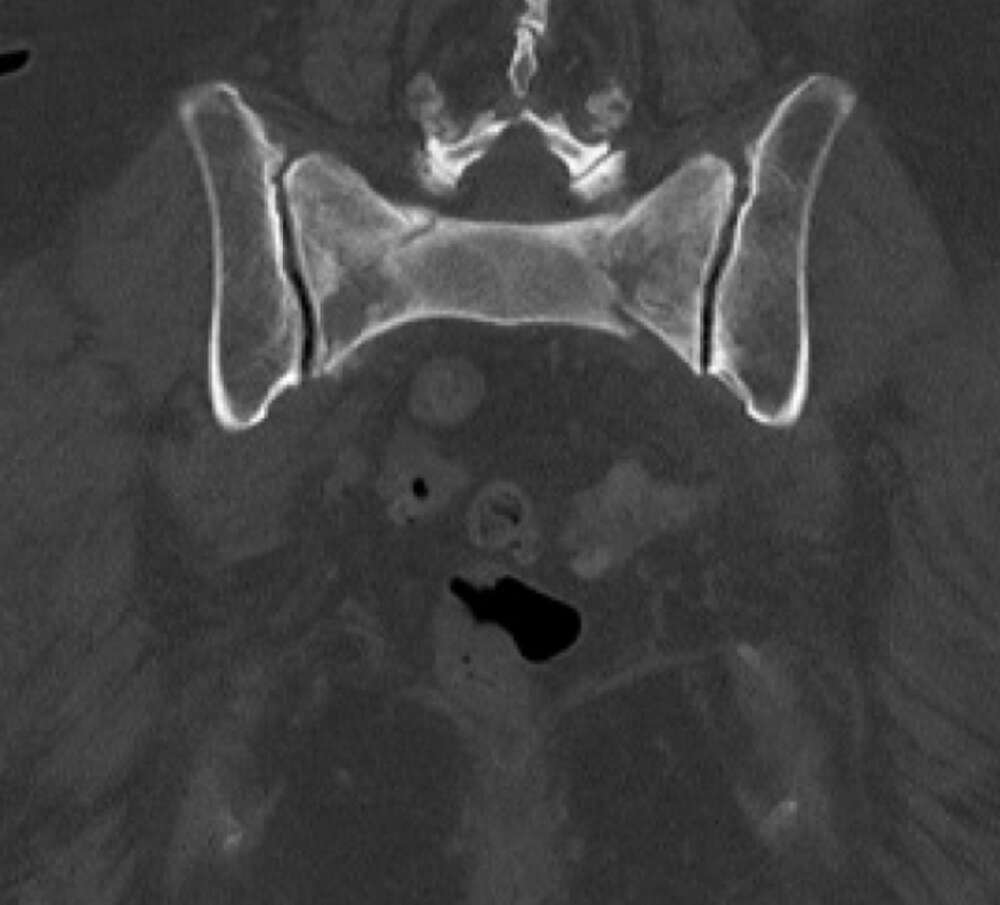

Diagnosis:

• Chronic Sacral U-type fracture with kyphotic deformity

• Anterior ring disruption

• Osteopenia